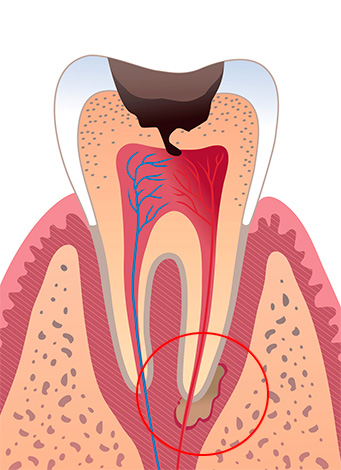

Con l'infiammazione alla radice, si sviluppa la parodontite. Allo stesso tempo, la polpa morta o i suoi resti si trovano nei canali del dente e il contenuto purulento del canale nella forma acuta della malattia si precipita verso le gengive, che provoca un forte dolore al dente, che non può nemmeno essere toccato.

La fornitura di cure di emergenza per la parodontite acuta è un compito importante per il dentista. Per fare questo, il medico apre il canale e lo lascia aperto per il pus, prescrivendo la soda e i risciacqui di sale. Una tecnica per il trattamento e il riempimento dei canali in una sola visita è possibile: per questo è importante creare una sterilità ideale nei canali, sigillarli in modo sicuro e, se indicato, prescrivere antibiotici.

Con la parodontite, il "nervo" muore davvero: tuttavia, inizia a decomporsi proprio qui. Il pus si precipita alla radice del dente, la radice del tessuto circostante diventa infiammata e gonfia, causando mal di denti terribile.

Con la pulpite, i denti dovrebbero sempre essere preservati, ma la parodontite è un argomento speciale. Le forme acute di parodontite sono più facili da trattare, il che non si può dire della possibilità di preservare i denti con le cisti. Tuttavia, anche la cisti della cisti è diversa, quindi, in ogni caso, vengono determinati la prognosi della malattia, la prospettiva del trattamento e l'importanza del dente nella dentatura e il morso nel suo insieme.